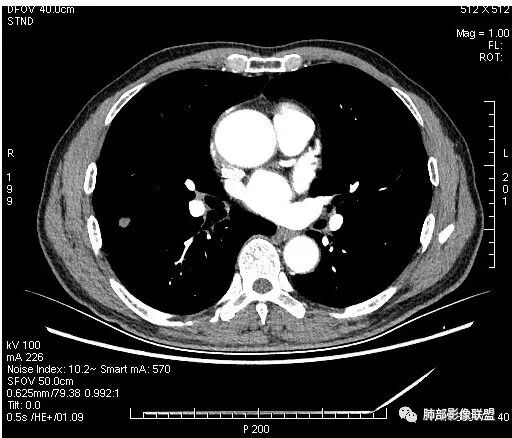

影像学改变:

1.右肺上叶后段类圆形结节影,密度不均,有坏死空洞,坏死比较彻底,内外壁都较清楚。

2.病灶有浅切迹,没有深分叶,毛刺大多细长且柔软。

3.可见棘状突起及胸膜牵拉,但未见胸膜凹陷。

什么意思?结节影有牵拉的动作,但似乎“出工不出力”,收缩力羸弱!

4.病灶轻到中度强化。病灶内血管走行较完好,病灶旁血管局部显示粗大。

5.支气管关系不确定。

6.灶周见小结节影(卫星灶),边界不甚清晰。